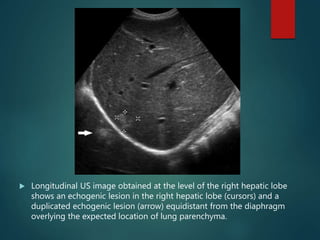

 Longitudinal US image obtained at the level of the right hepatic lobe

shows an echogenic lesion in the right hepatic lobe (cursors) and a

duplicated echogenic lesion (arrow) equidistant from the diaphragm

overlying the expected location of lung parenchyma.